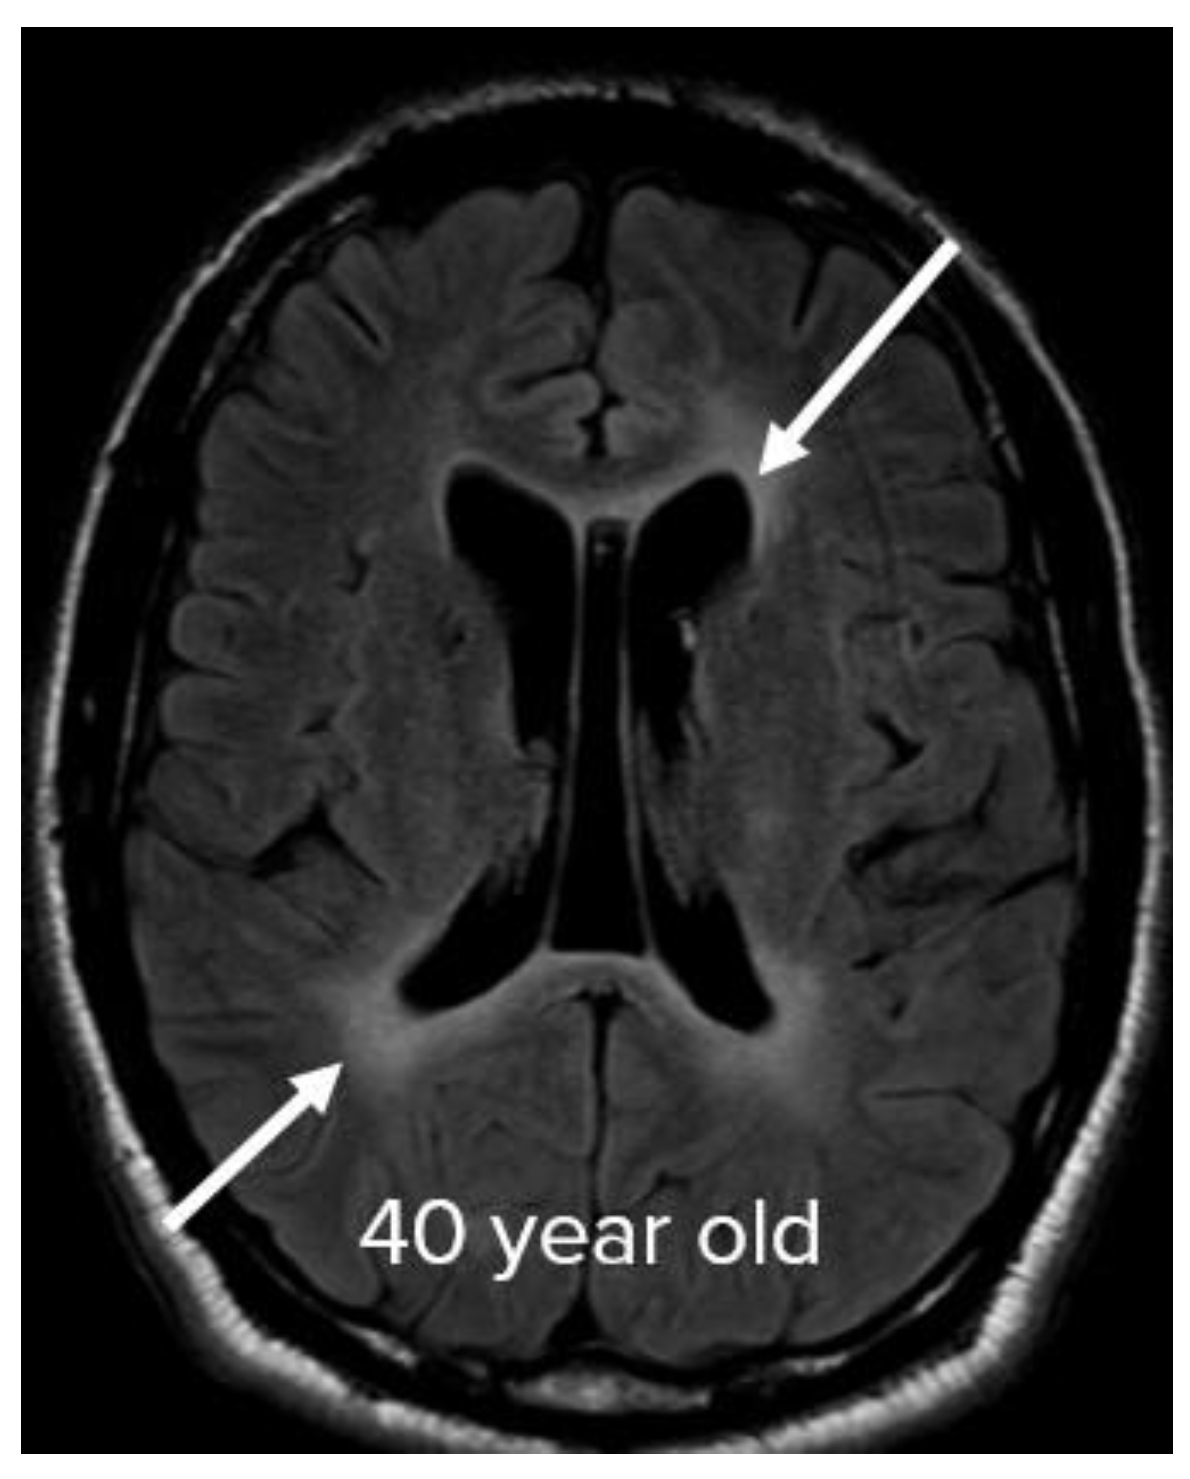

- Kishfy, L.; Casasola, M.; Banankhah, P.; Parvez, A.; Jan, Y.J.; Shenoy, A.M.; Thomson, C.; AbdelRazek, M.A. Posterior reversible encephalopathy syndrome (PRES) as a neurological association in severe COVID-19. J Neurol Sci. 2020, 414, 116943. [Google Scholar] [CrossRef] [PubMed]